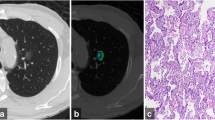

Representative cases of pure ground-glass nodules. a Adenocarcinoma-in-situ in a 42-year-old man. Two-dimensional average diameter was 7.6 mm, and nodule mass was 0.11 g (contrast-enhanced CT). Both measurements corresponded well with the diagnosis. b Adenocarcinoma-in-situ in a 47-year-old man. The two-dimensional average diameter was 13.3 mm, and nodule mass was 0.49 g (non-enhanced CT). Based on the volumetric measurements, invasive adenocarcinoma was more likely than a preinvasive lesion. c Adenocarcinoma in a 45-year-old male. Two-dimensional average diameter was 9.2 mm, and nodule mass was 0.17 g (non-enhanced CT). Volumetric measurements, which are suggestive of a preinvasive lesion, were discordant with the diagnosis. Invasive component size was 6 mm in this lesion